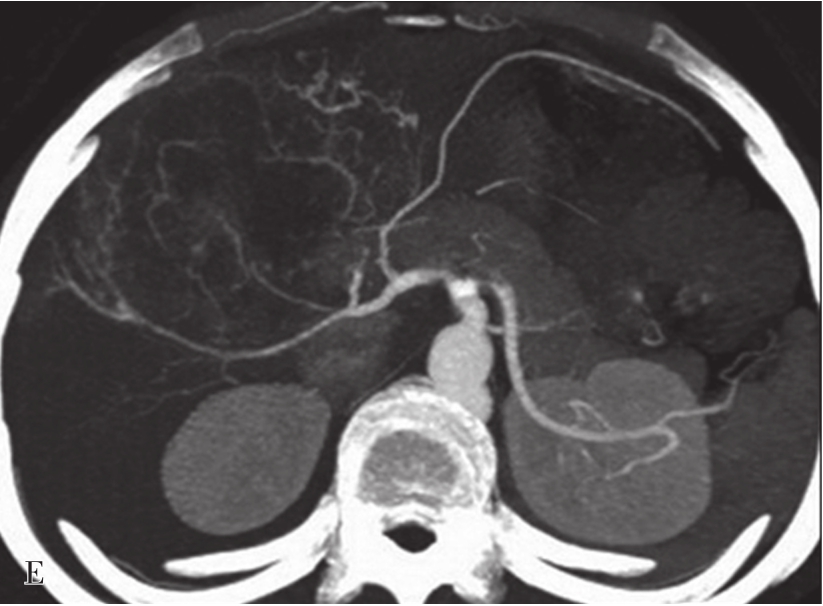

(2)CT表现:

巨块型和结节型平扫表现为单发或多发、圆形、类圆形或不规则形肿块,呈膨胀性生长,绝大多数肝癌边缘有假包膜,因而多数瘤灶边界清楚,这是肝细胞癌CT诊断重要征象;弥漫型者结节分布广泛,境界不清;小肝癌表现为肝实质内3cm以下类圆形肿块。肿块多数为低密度,少数表现为等密度,或在脂肪肝背景衬托下可呈高密度。巨块型肝癌可发生中央裂隙状坏死而出现更低密度区,合并出血或发生钙化,则肿块内表现高密度灶;有时肿块周围出现小的结节灶,称为子灶。多数肝癌主要由肝动脉供血,增强扫描动脉期,病灶通常出现明显的斑片状、结节状早期强化;在门静脉期,门静脉和肝实质明显强化,而肿瘤无或仅少量门静脉供血则强化程度迅速下降;平衡期,肝实质继续保持较高程度强化,肿瘤强化程度则继续下降而相对低密度表现,增强过程表现典型的“快进快出”的特征性改变(图5-21-38)。少数肝癌为门静脉供血为主者,其强化方式相对不典型。如在动态CT系列图像上分别测定CT值并绘制时间-密度曲线,可见肝癌强化的时间-密度曲线呈速升速降形曲线。肿瘤的假包膜一般呈延迟强化表现。有门静脉、肝静脉或下腔静脉癌栓者则增强门脉期或静脉期出现静脉内低密度充盈缺损,部分患者可见转移性腹膜后和肝门区的淋巴结肿大,以及远处转移。

图5-21-38 HCC患者的CT平扫及增强图像

A.CT平扫图像,肝右前叶内可见巨块状稍低密度影,大小约10.5cm×8.3cm,CT值为36~46HU,其内密度不均,界限欠清,病灶内可见更低密度影;B.增强扫描动脉期,病灶不均匀强化,CT值约69HU,并见多量小刷状不成熟肿瘤血管影(箭头);C.增强扫描门脉期图像,病灶密度略低于肝脏实质,CT值约68HU,病灶假包膜厚薄不均(箭头);D.3min延迟期图像,随着时间的延长,病灶密度低于肝脏实质,CT值64HU,中央低密度区未见明显强化;E.动脉期最大密度投影法重建图像示肝动脉分支明显增多供应病灶